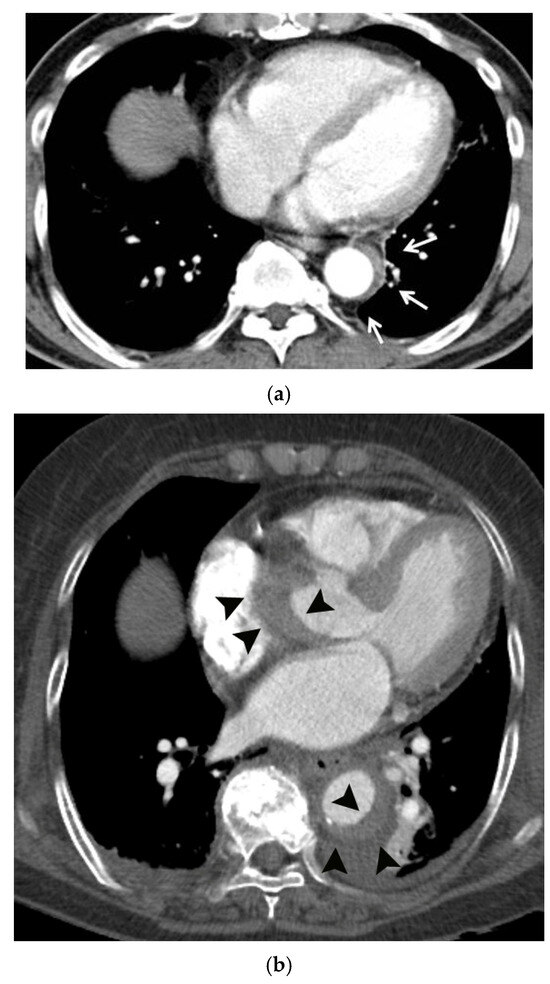

The Middle Meningeal Artery (MMA) occupies a pivotal role in the pathophysiology of migraine, functioning as a vascular and neuroimmune interface that precipitates the characteristic pulsatile pain. The inhibition of this pathophysiological cascade has been investigated as a therapeutic strategy. However, fewer than a dozen centers globally have disseminated procedural or mechanistic data. Given the nascency of this field and the imperative for standardization, the present review synthesizes mechanistic and clinical evidence underpinning intra-arterial pharmacological modulation of the MMA for migraine management. Methods: A focused narrative review was undertaken, drawing upon select but influential studies from pioneering research groups investigating intra-arterial interventions targeting the MMA. The extant literature was thematically categorized and organized according to the loci of cascade interruption and their corresponding clinical outcomes. Results: Since 2009, intra-arterial therapies for severe headache syndromes have evolved, initially utilizing nimodipine for vasospasm-related headaches, progressing to verapamil for reversible cerebral vasoconstriction, and more recently, lidocaine for refractory or status migrainosus, occasionally in conjunction with MMA embolization. Contemporary research uses language that conceptualizes migraine as an immunologically mediated neurovascular disorder, as opposed to a purely vascular or neuronal entity. Recent investigations have identified interleukins such as Interleukin-1β, Tumor Necrosis Factor-α, and Interleukin-6 as critical amplifiers of trigeminovascular activation. Purinergic signaling through the P2X3 receptor and the P2Y13 receptor, in conjunction with pituitary adenylate cyclase-activating polypeptide and vasoactive intestinal peptide pathways, has been implicated in the modulation of MMA excitability and neuropeptide release. The development of novel calcitonin gene-related peptide receptor antagonists, such as zavegepant, further substantiates the artery’s significance as a pharmacological target. Conclusions: These findings support a shift toward immune-modulating intra-arterial therapeutic strategies, with migraine interventions targeting cytokine and neuroimmune signaling within the MMA, rather than relying exclusively on vasodilatory mechanisms.